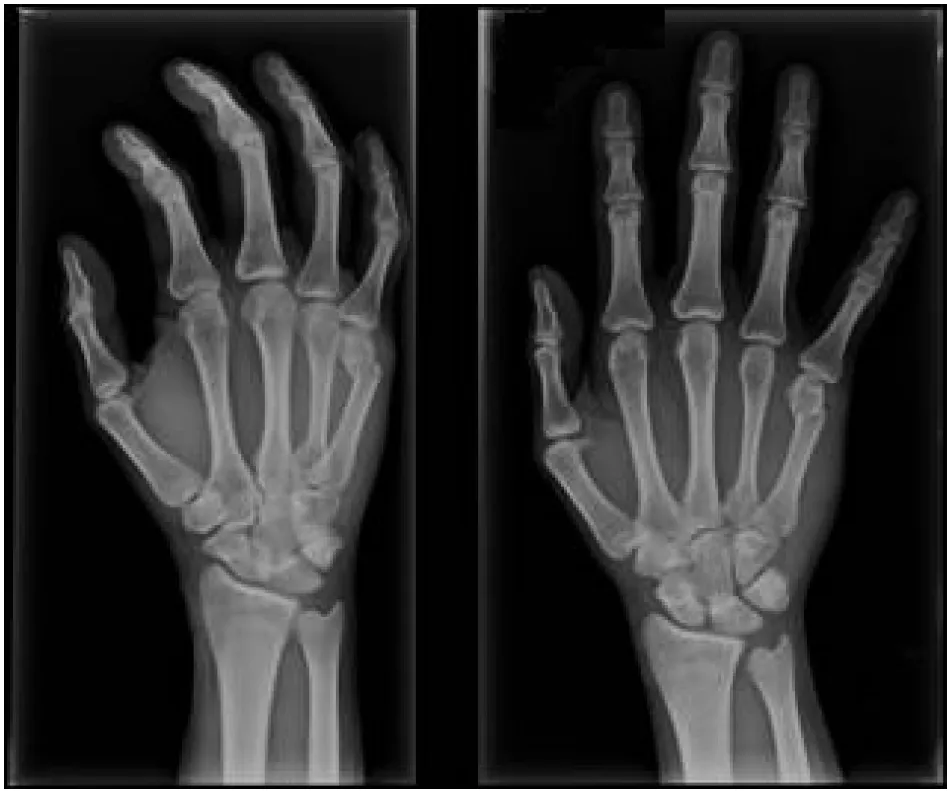

這張X光片最關鍵的線索是小指遠端指骨(distal phalanx)的背側基部有一小塊骨頭被拉扯下來,這就是典型的槌狀指骨折。